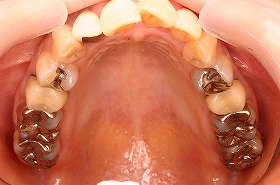

歯の矯正治療 症例ビフォー&アフター

ご覧の症例は前歯のねじれ出っ歯を矯正治療でキレイにし、

さらに、奥歯のぎらつく銀歯をセラミックにつめなおしたケースです。

歯並びキレイになると、つめものの色も気になってくるようですね。

矯正治療と合わせてつめものを詰め替える方も多くいらっしゃいます。

今回の治療費 表側矯正治療全顎 装置費80万円+税 調整1回5000円+税 セラミック治療12本856,000円+税